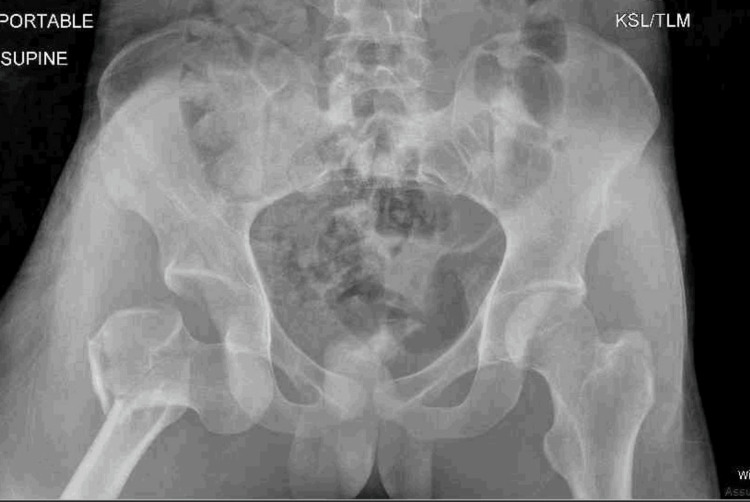

Direct inferior hip dislocation is the rarest type, sometimes referred to as luxatio erecta. To the author's knowledge, an adult inferior hip dislocation with an associated displaced intertrochanteric fracture has only been reported once in the literature. Accordingly, there are few described treatment options for this injury. An 18-year-old male presented after a motor vehicle collision with an inferior hip dislocation and an associated ipsilateral intertrochanteric hip fracture. He was taken to the operating room urgently for the reduction of the dislocation and definitive treatment. In this case, a fracture table was utilized along with a Schanz pin to reduce the hip dislocation and for the reduction and intramedullary nailing of his intertrochanteric fracture.

Abstract Image